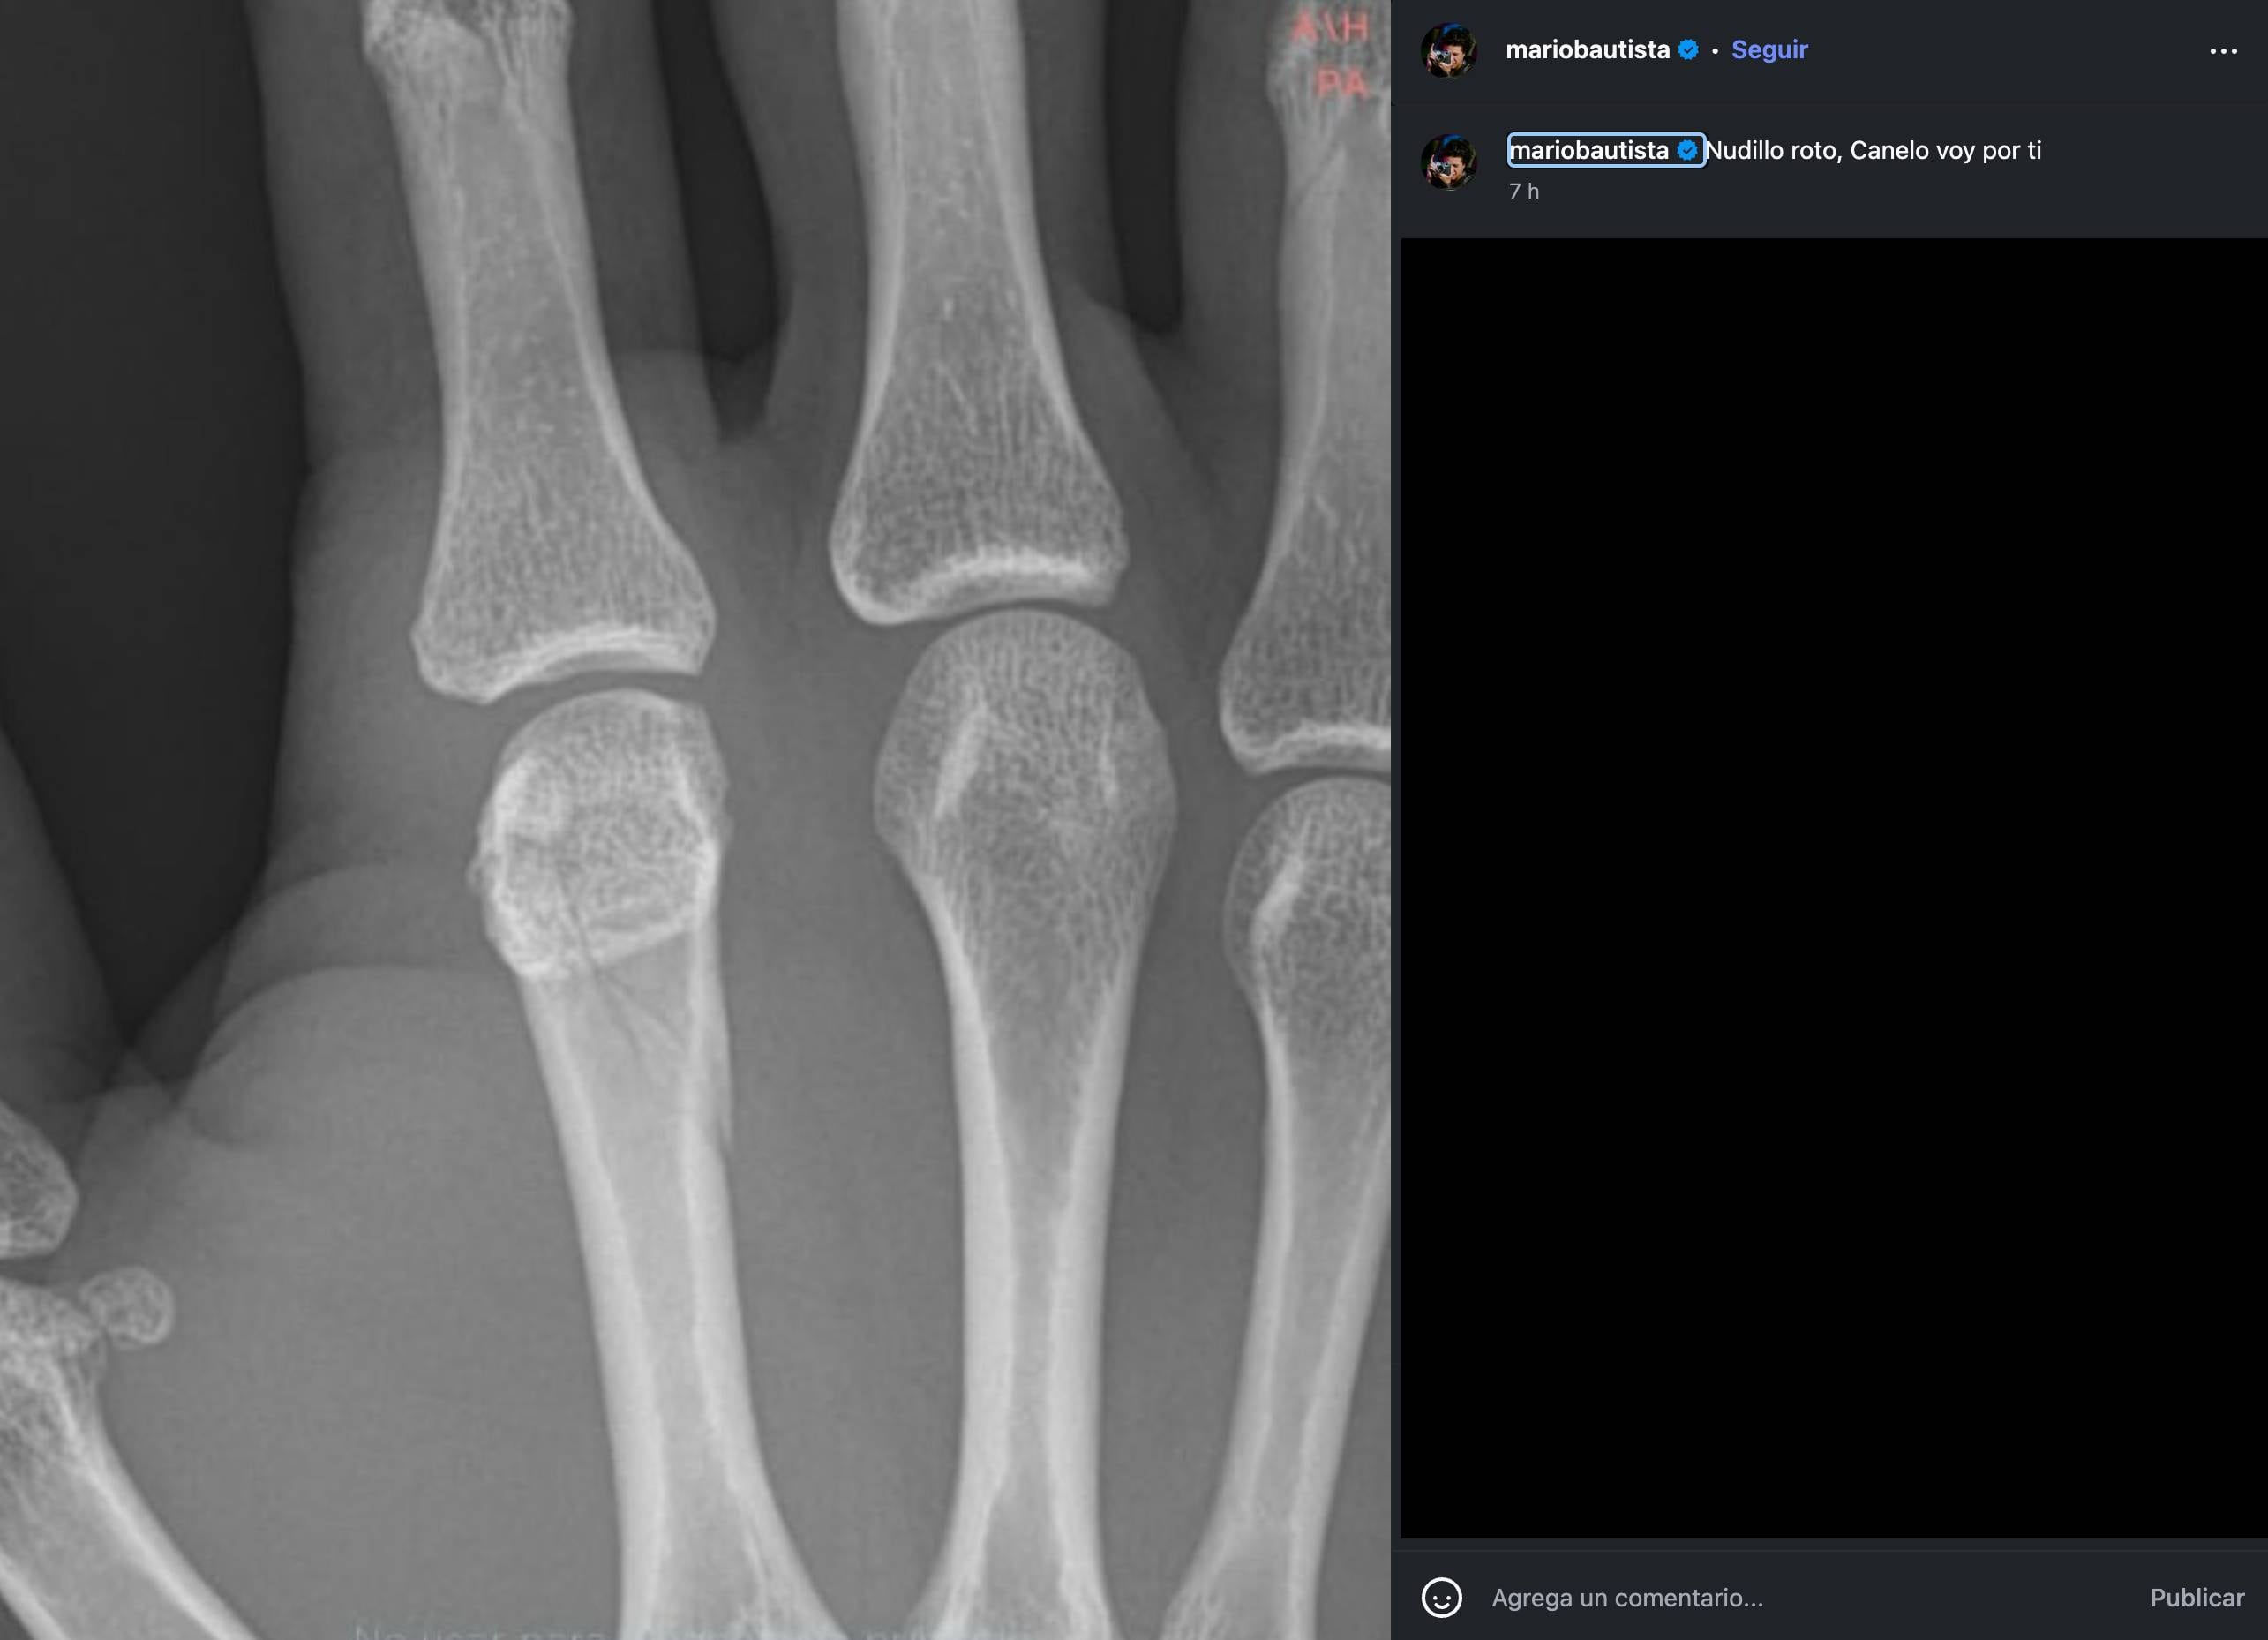

Mario Bautista reveló al día siguiente de la pelea en Supernova: Génesis que se había fracturado el nudillo.

“Nudillo roto, Canelo voy por ti”, escribió en la descripción de su publicación en Instagram, donde compartió una radiografía de su mano y se percibía la lesión.